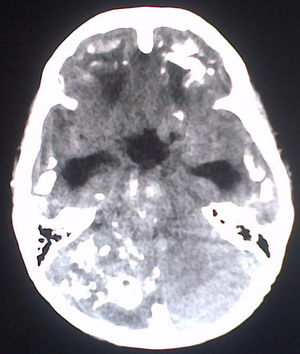

以下是引用jiajie在2009-2-3 20:02:00的发言:[br]脑室周围白质区可见大量斑片状钙化,部分融合成带状,双侧侧脑室及第三脑室扩大。[br]考虑弓形体原虫感染。(先天性宫内感染、torch综合症)

以下是引用lkc8963在2009-2-3 21:15:00的发言:[br]临床眼睑可见静脉扩张,ct双侧眼上静脉亦示扩张,颅内钙化以皮层\\软脑膜为主而不是位于白质和室管膜,再加上静脉窦异常,还是应该考虑静脉血管瘤病,可能为较复杂的血管畸形.

以下是引用卜一在2009-2-4 9:21:00的发言:[br]sturge-weber综合征:面部三叉神经分布区的毛细血管性或海绵状血管瘤以及同侧枕、顶或额叶软脑膜的血管瘤(以静脉性为主)。脑皮质,特别是第二三层,毛细血管可有增厚和钙化。局部发生层状坏死、神经细胞脱失、萎缩、胶质细胞增生及钙盐沉着。可根据面部典型分布的特征性皮痣作出诊断。头颅ct:发现面部血管瘤同侧的脑内病理钙化影,呈双层线条波浪形、脑回形或树枝形。本例支持:sturge-weber综合征![br]